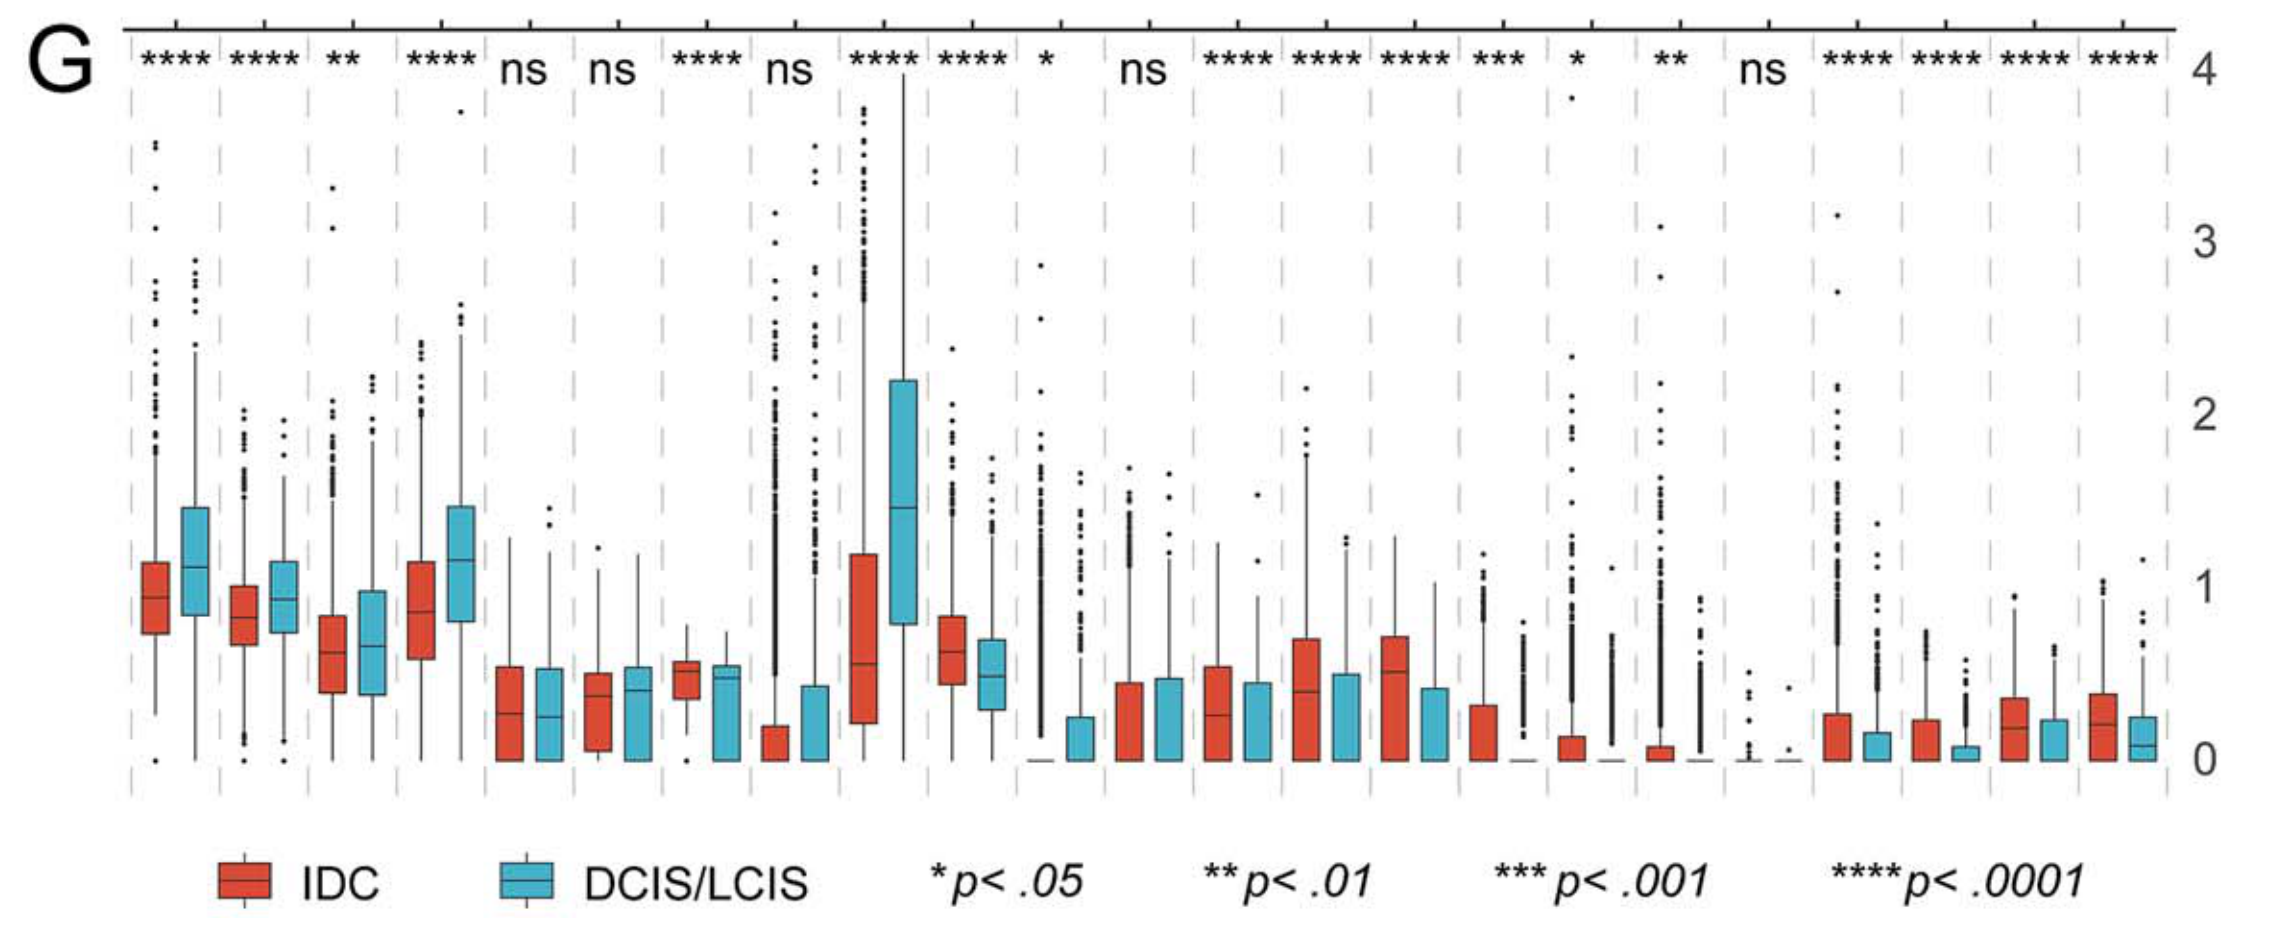

Li X. et al. - 2025

SPEX: A modular end-to-end platform for high-plex tissue spatial omics analysis

Condition Dimension

Categorical

Data Components

Biological AnnotationGene Expression Matrix

Metadata

None

Modality

Proteomics

Resolution of observation

Cellular

Visualized Elements

Statistic

How does expression of a gene differ across patient categories?

Biological

Molecular

Abstraction

Complete

Chart Type

Boxplot

Communicative/Contextualization

Annotation

Comparative Design

Juxtaposition

Layout

Linear

Scalability Strategy

Summay/Aggregate